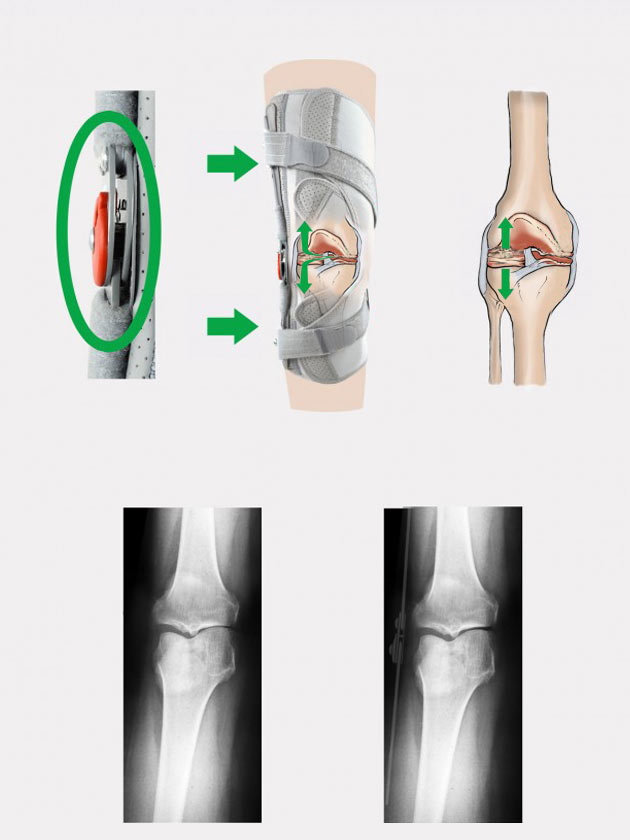

Шина 1R Orthodesign

Szyna ortopedyczna 1R orthodesign, to nowatorskie podejście do tematyki szyn ortopedycznych z regulacją kąta zgięcia i wyprostu. Innowacyjność szyny polega na tym, że w zegarze o średnicy nie przekraczającej 30 mm, zastosowaliśmy regulację kąta zgięcia i wyprostu co 15 stopni. Dodatkowym atutem szyny jest to, że regulacja odbywa się nie przy użyciu wkrętów imbusowych, jak to się odbywało w poprzedniej generacji szyny, lecz za pomocą wkładanych stalowych nitów, które dla ułatwienia wyjmowane są z gniazd kątowych przy użyciu załączonego do szyn magnesu. Wisienką na torcie jest pierścień blokujący, który dzięki systemowi zapadkowemu nie pozwoli na samoczynne przestawienie się wcześniej ustawionego kąta. W ortezach kolana szyny mają odsadzenie goleniowe, co pozwala na bardziej precyzyjne dopasowanie ortezy kolana, a co za tym idzie dokładniej realizują regulację ruchomości stawu, w pozostałych wyrobach zaś, ortezy mają formę prostą. Od spodniej strony zegara zamontowano owalny element do którego doklejono gripper niezbędny do przymocowania do zegara miękkich poduszek bocznych 3D. Szyny te, przy użyciu klucza ortopedycznego będącego w ofercie Reh4Mat, mogą być w niektórych przypadkach indywidualnie dopasowane do kształtu kończyny pacjenta, poprzez ich lekkie dogięcie. Pobierz instrukcję regulacji szyny 1R orthodesign